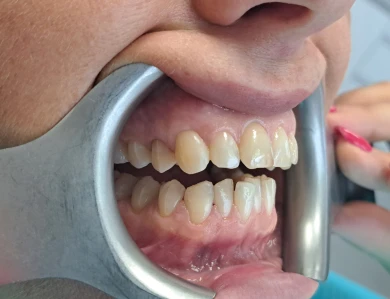

Improving Aesthetics After Orthodontic Treatment

Our patient had multiple discolored teeth and composite fillings placed many years ago. After successful […]